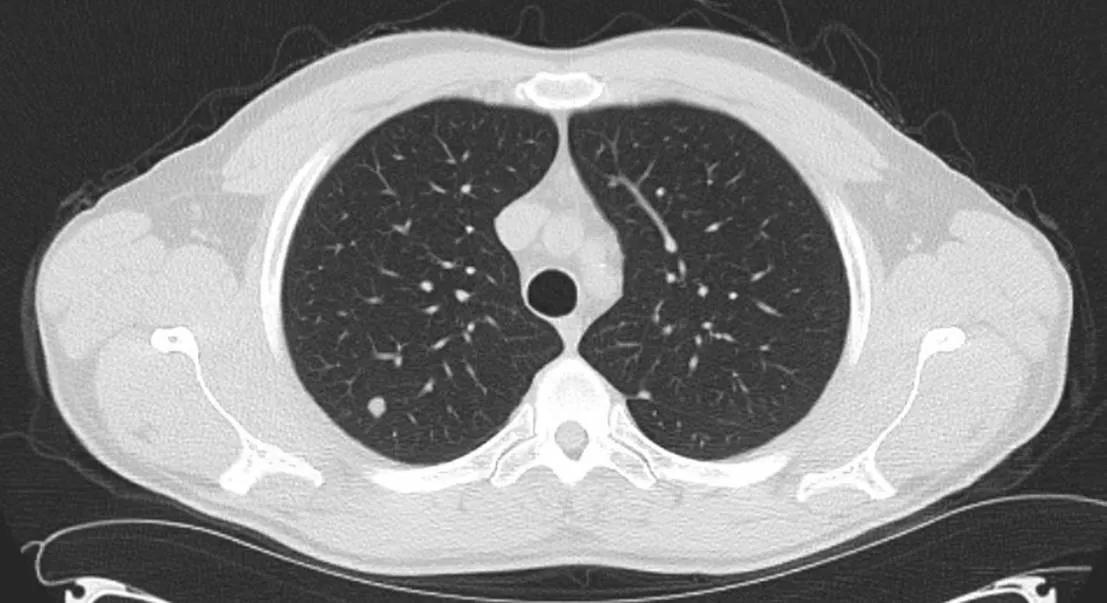

Lung nodules are one of the most common incidental findings seen on radiology exams. Concerns arise when these nodules go unrecognized as may occur if the imaging study is not performed for a pulmonary complaint or if the ordering provider is not involved in the longitudinal care of the patient. By the time the nodule is recognized, early-stage lung cancer may have become more advanced and more difficult to cure.

To date, our pilot program with the HVTI has identified approximately 100 patients per month with incidental nodules deemed actionable by our radiologists. The flowchart shows branch points in patient management from the time they are identified to an endpoint in their care (Figure). Approximately 3% to 4% of those seen by program providers have been diagnosed with a lung cancer.

Lung nodule management program.

Figure. The flowchart shows branch points in patient management from the time they are identified to an endpoint in their care. Approximately 3% to 4% of those seen by program providers have been diagnosed with a lung cancer.